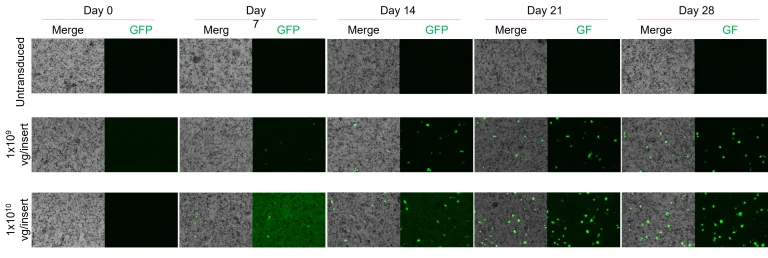

Transduction efficiency in RPE

Dose- and time-dependent increase in GFP signal in AAV-transduced RPE. Percentage of GFP-positive cells over 28 days post-transduction with AAV5-CAG-EGFP:WPR at two different doses. Scale: 150 µm. Image Credit: Newcells Biotech